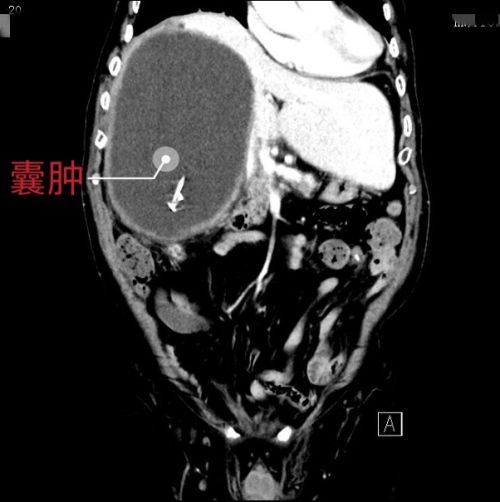

ct显示右肝巨大囊肿。

家住长沙市开福区的黄大爷今年93岁,1年前因右上腹胀痛,在外院诊断为“肝脏囊性疾病”。家属考虑老人高龄,手术风险大,选择进行相对保守的治疗措施:一年之内先后进行了四次囊肿穿刺引流和硬化剂注射,每次放出囊液超过2000ml。然而,每次穿刺后不久,腹腔囊性包块都会再次出现,导致老人反复腹胀,影响食欲,苦不堪言。2020年5月15日上午,老人因囊肿体积大影响呼吸和进食,在家人的陪伴下慕名来到捷克论坛 肝脏外科门诊就诊。段小辉主任医师结合临床表现和检查结果考虑肝脏囊性肿瘤,当即收入肝脏外二科病房。

入院第二天,患者在B超引导下行囊肿穿刺引流,引流出囊液1800ml(约2公斤),黄大爷呼吸得到明显改善。但仅通过引流只能缓“燃眉之急”,因囊肿位于整个右半肝,在毛先海教授的组织下,段小辉主任医师团队仔细评估病情后,考虑患者有手术指征,联合老年医学科和麻醉科专家完善术前评估。患者及家属亲眼见证了医院在高龄患者手术方面的综合保障能力,决心行外科手术治疗。5月24日,充分完善术前准备后,在毛先海教授的指导下,段小辉主任医师及王子承主治医师为患者行右半肝切除。麻醉科廖孝芸主任医师在积极保障患者重要脏器血供的前提下,控制低中心静脉压。术中的加速康复外科措施保证了肝切除过程中顺利进行,虽然患者之前反复硬化剂注射,炎症粘连较重,但术中出血不到200ml,手术顺利结束。